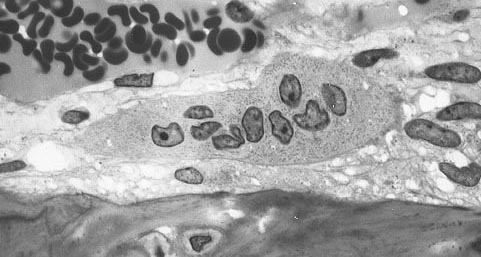

back osteoclast

Source: Osteoclast